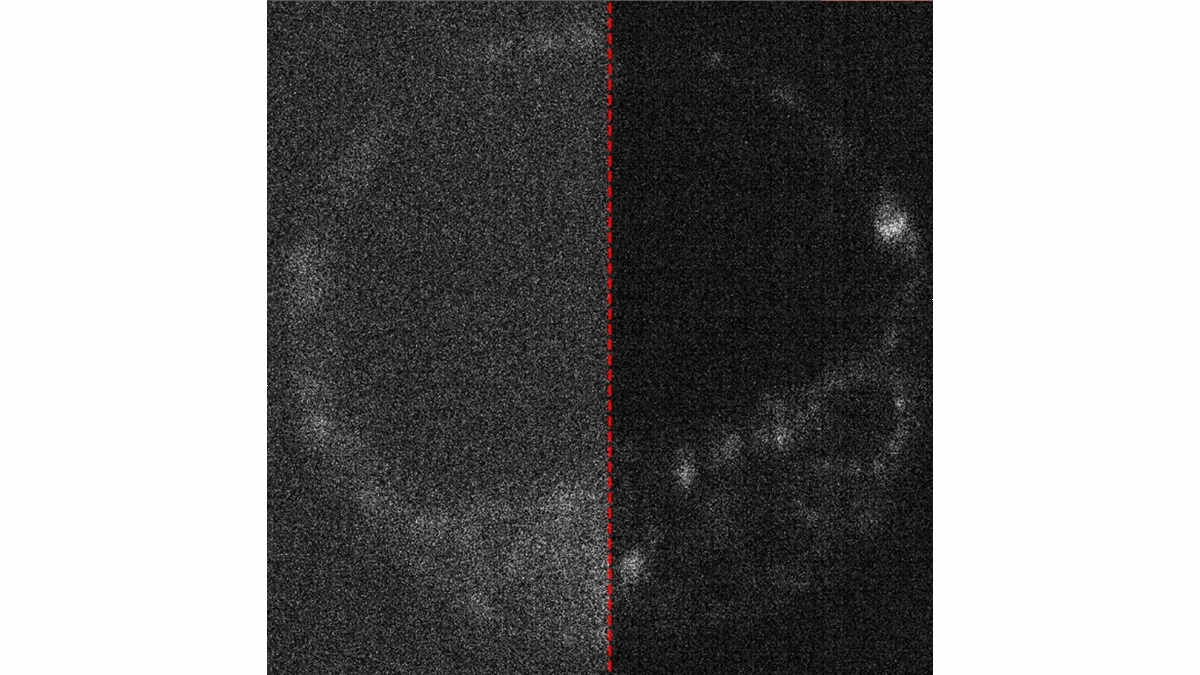

Blurry image of mouse embryo divided in half

Image of a live mouse embryo with and without optimised capture. Credit: University of Adelaide.

“A large part of the project involved developing a method to fairly compare the image quality across different cameras,” Peterkovic adds. “We even explored how AI can be used to remove noise from the captured images, which is essentially static because the camera struggles to capture enough light.”